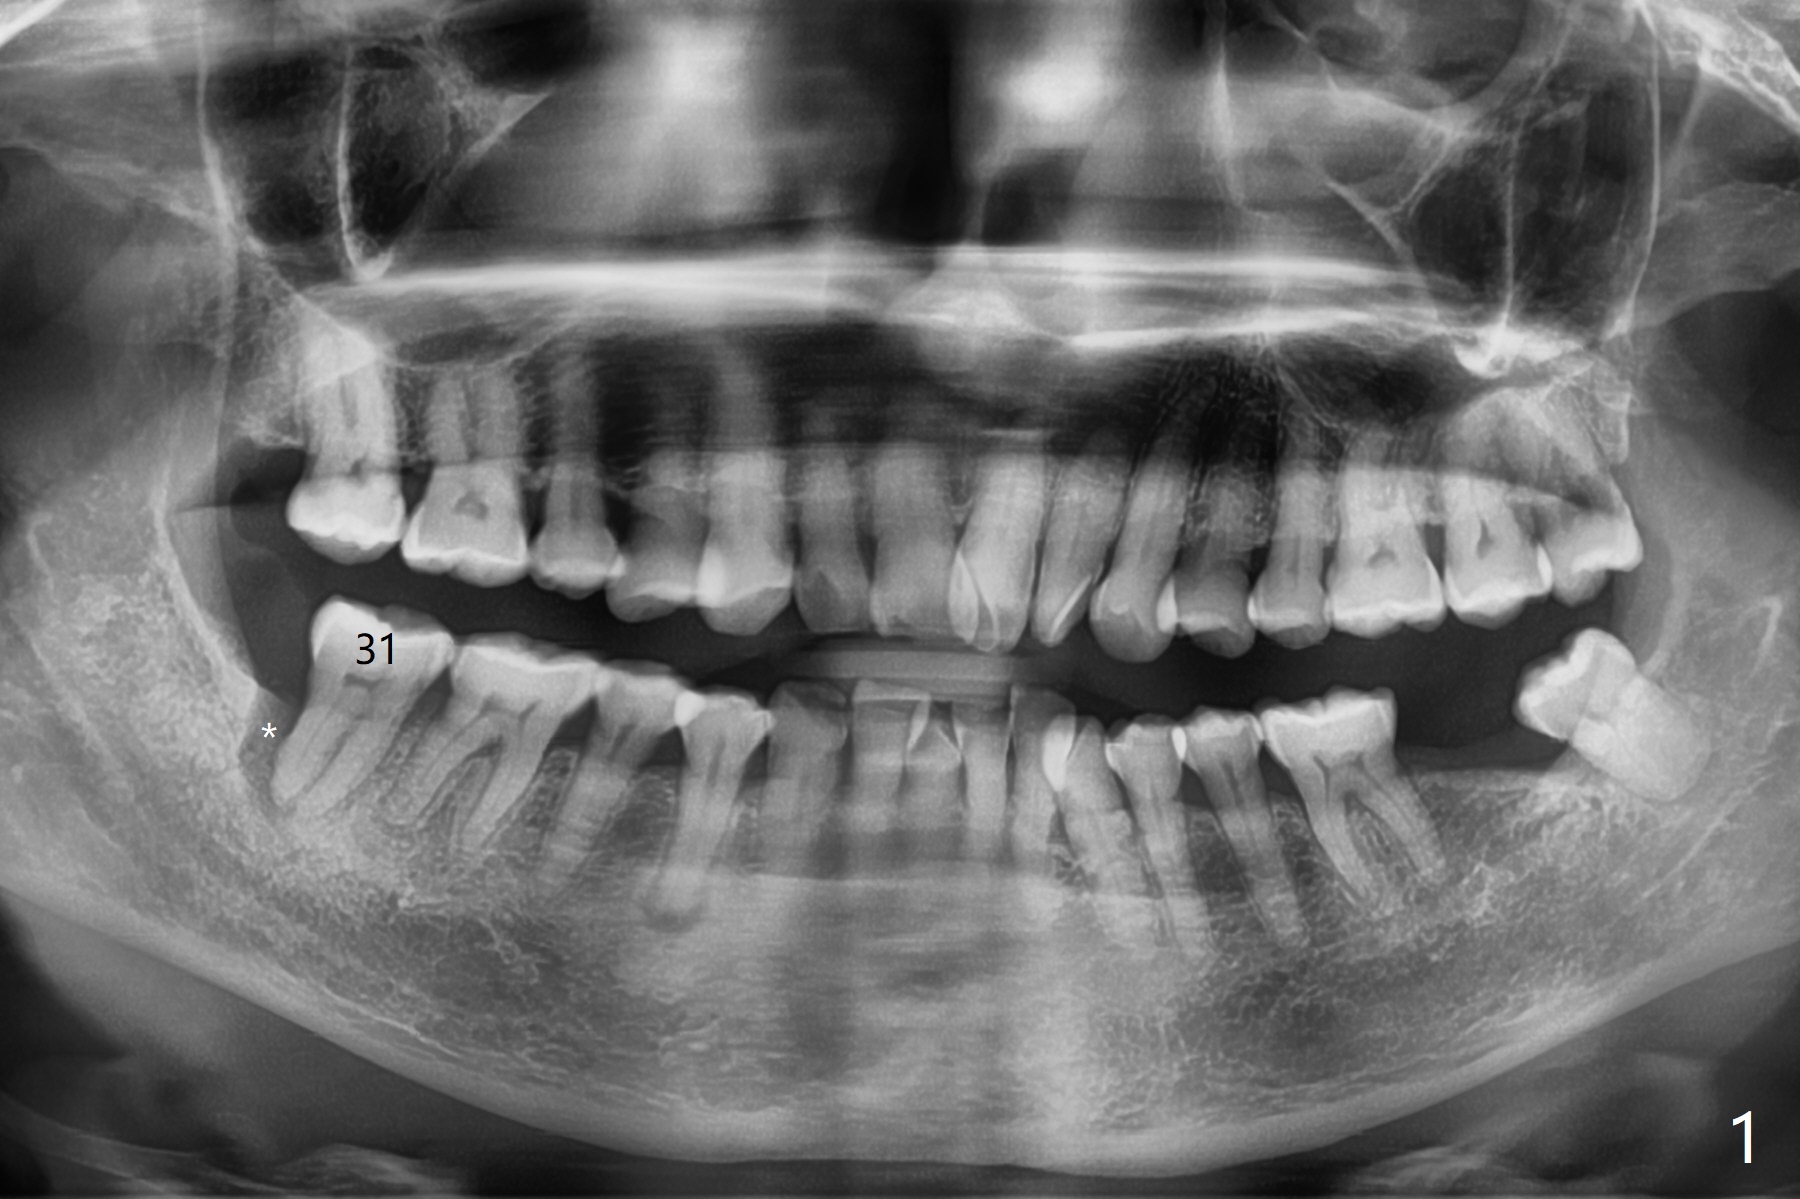

今天特别忙,第一位病人深洗后需要拔除智齿,事先准备使用胶原塞,但是术后发现缺损太大,需要植骨,匆忙使用GEM21S与细颗粒骨粉调袢,需要用大号输送器送到口内,骨粉容易散开,不便利。几个小时后,63岁女急诊要求拔除右下第二磨牙(图一),开始我们准备也使用GEM21S,但是没有大号输送器,改为抽血,制备粘性骨粉,很方便用镊子将骨块输送到牙槽窝(图二:G),上面覆盖PRF膜和不可吸收膜,PTFE缝线,由于缝合比较密,不需要牙周敷料。